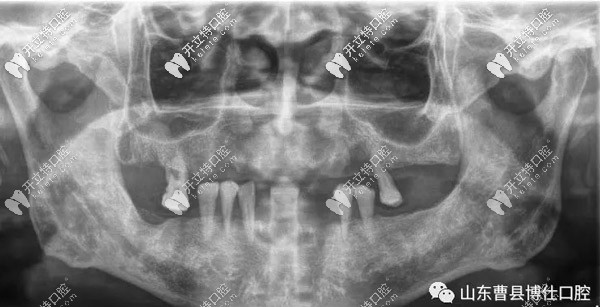

口腔上下只剩7顆牙,對飲食帶來了很多不便,經(jīng)檢查發(fā)現(xiàn)徐大爺因患牙周病導(dǎo)致牙齒松動、牙齦萎縮、牙槽骨吸收。

經(jīng)過博仕口腔的于院長與山東腔醫(yī)院、濟(jì)寧醫(yī)院口腔科和省外醫(yī)生的診斷,采用了7D微創(chuàng)速導(dǎo)種植技術(shù)。